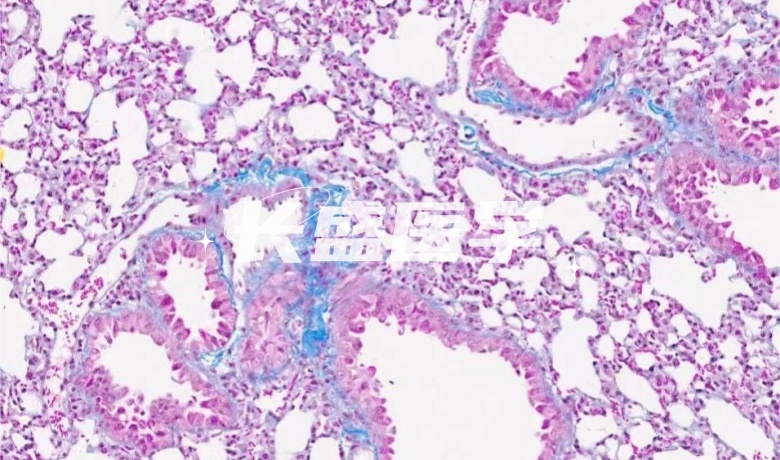

Masson染色

染色Masson时,胶原纤维会显现出蓝色或绿色,因其被染料苯胺蓝或亮绿染色。反之,肌纤维会呈现红色,因其被酸性品红和丽春红染料所着色。这种差异的产生与阴离子染料的分子大小以及组织对染料的渗透性密切相关。

Masson染色是一种常见的组织学染色方法,其通过使用不同大小的阴离子染料,针对组织的渗透性和化学成分的差异,将胶原纤维、肌纤维和红血细胞进行染色。在该方法中,胶原纤维被较大分子的阴离子染料着色,呈蓝色或绿色;肌纤维则被中等大小的阴离子染料着色,呈红色;而红血细胞则被最小分子的阴离子染料着色。这种染色方法具有很高的临床应用价值,因为它可以快速准确的显示出不同的组织成分,从而帮助医学专业人员诊断和治疗不同的疾病。